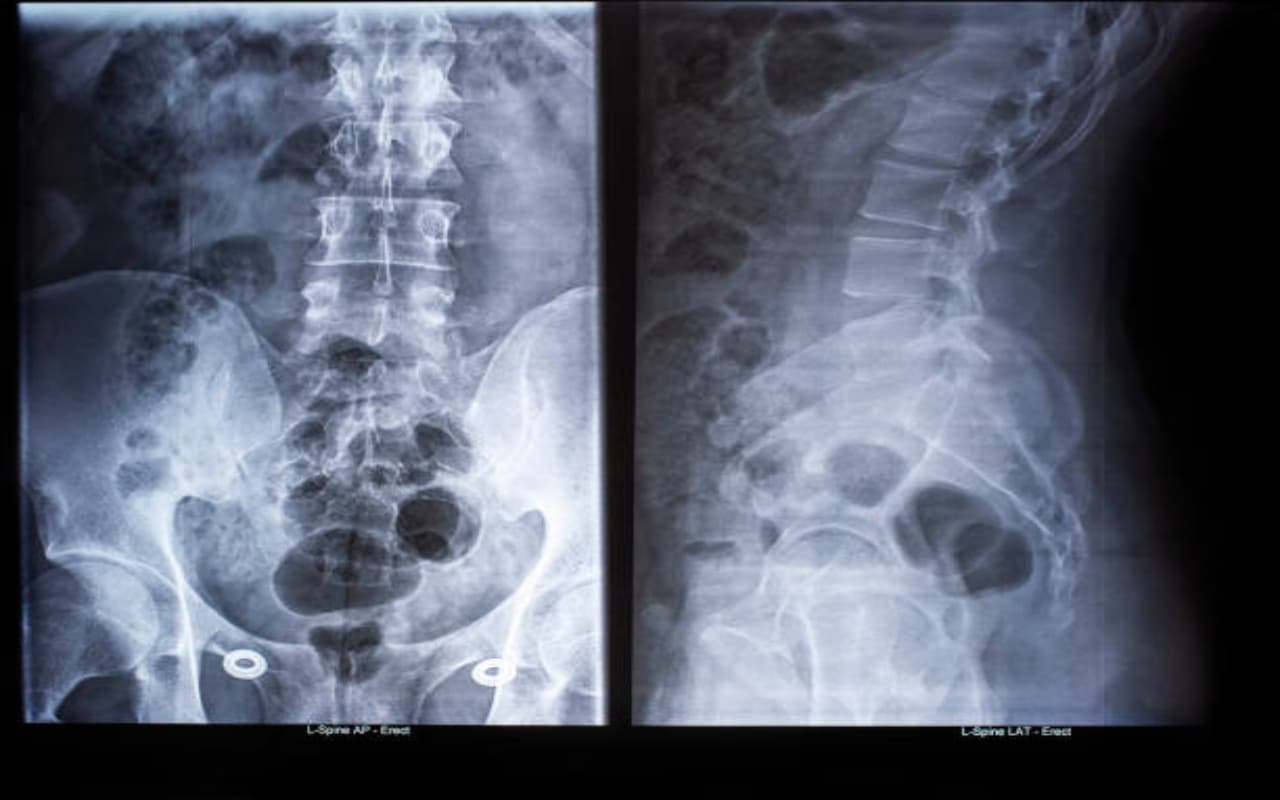

हर इंसान को अपने लिए या कई बार अपनों के लिए मेडिकल हेल्प की जरूरत होती है. जहां उन्हें या घरवालों या फिर बेहद करीबी लोगों के लिए कभी एक्स- रे, एमआरआई और सीटी स्कैन जैसी जांच प्रक्रियाओं की जरूरत पड़ती है. रेडियोग्राफी एक ऐसा शब्द है जो उन अध्ययनों को शामिल करता है जिनमें एक्स-रे तकनीकों की मदद से शरीर के आंतरिक भागों के दृश्य की आवश्यकता होती है. दूसरे शब्दों में, एक्स-रे परीक्षाएं चिकित्सीय निदान के लिए आंतरिक अंगों या हड्डियों की छवियां बनाती हैं. एक विशेष उपकरण थोड़ी मात्रा में आयनकारी विकिरण उत्सर्जित करता है, जो शरीर से होकर गुजरता है और एक विशेष गैजेट द्वारा पकड़ लिया जाता है. एक्स-रे छवि इस प्रकार दिखाई देती है. विकिरण की डोज जांच किए गए क्षेत्र पर निर्भर करती है.उदाहरण के लिए, छोटे क्षेत्रों, जैसे बाहों, को रीढ़ जैसे बड़े क्षेत्रों की तुलना में कम डोज मिलती है. औसतन, रेडिएशन की डोज एक सप्ताह के भीतर आपको पर्यावरण से प्राप्त होने वाली मात्रा से अधिक नहीं होती है. हमारी हड्डियों में मौजूद कैल्शियम रेडिएशन को रोकता है, यही कारण है कि स्वस्थ हड्डियाँ छवियों में या तो सफेद या भूरे रंग की दिखती हैं. इस तथ्य के कारण कि विकिरण आसानी से हवा से गुजरता है, स्वस्थ फेफड़े हमेशा काले दिखते हैं।